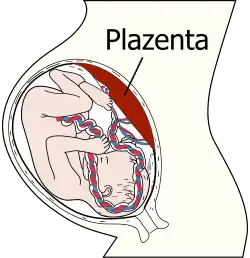

Die körperliche Entwicklung während der Pränatalzeit – insbesondere die des Gehirns – ist von besonderer Bedeutung für die Pränatalpsychologie. In den ersten acht Wochen nach der Befruchtung der Eizelle wird das heranreifende Kind als Embryo bezeichnet. Nachdem die inneren Organe ausgebildet sind (ab der neunten Entwicklungswoche) wird die Bezeichnung Fötus (oder Fetus) verwendet.

Francis J. Mott (1901–1980) war ein Schüler von Fodor. Er war wohl der erste Theoretiker, der sich mit der Plazenta als erstem Objekt des Fötus auseinandersetzte.[40] Er schrieb, dass der Fötus die Plazenta als „blutsaugendes Monster“ fürchte oder auch als „Fütterer“ oder „Lebensspender“ erlebe.[41] Er ordnete pränatalpsychologische Aspekte in einen größeren mystischen Bezug zur Ordnung des Universums ein, was sein Werk letztlich zu einem hochspekulativen, quasi-religiösen Entwurf macht.

Wichtige Impulse für die tiefenpsychologische Betrachtung der Pränatalzeit stammen aus der LSD-Forschung. Der deutsche Psychiater Hanscarl Leuner (1919–1996) und der tschechische Psychiater Stanislav Grof (* 1931) leisteten hier Pionierarbeit. 1962 beschrieb Leuner in Die experimentelle Psychose die Erlebnisse seiner Patienten unter LSD-Einfluss. Ohne dass er damals selbst eine Beziehung zu pränatalem Erleben des Fötus herstellte, wirken diese halluzinativen Szenen wie Reaktivierung prä- und perinataler Erlebnisse.[42] Manche Patienten halluzinierten beispielsweise Kämpfe mit Kraken oder Spinnen, die von Pränatalpsychologen als prototypische Symbole der Plazenta verstanden werden.[43] Grof interpretierte in Topographie des Unbewussten von 1975 das Erleben seiner Patienten im LSD-Rausch unmittelbar mit Hilfe seiner pränatalpsychologischen Konzeptionen (den sog. „perinatalen Matrizen“).[44] Wie zahlreiche Pränatalpsychologen stellte er im Lauf seiner Theorieentwicklungen zunehmend diese pränatalpsychologischen Überlegungen in einen quasimystischen Zusammenhang mit umfassenden Weltentwürfen. Gleichwohl beeinflusste Grof die Arbeit von deMause, der die metaphysischen Implikationen nicht übernahm.

Der US-amerikanische Sozialwissenschaftler Lloyd deMause (1931–2020) kompilierte in einem Essay von 1981 sowohl die diversen psychoanalytischen Theorieansätze zur Pränatalzeit als auch die damals bereits zahlreichen empirischen Befunde zu den physiologischen Besonderheiten der menschlichen Ontogenese. Eine große Rolle spielt dabei die Versorgung des Fötus durch die Plazenta, insbesondere mit Sauerstoff. Daraus entwickelte deMause seinen eigenen Ansatz, der nach wie vor den umfassendsten Entwurf einer Pränatalpsychologie darstellt.[45] Er geht davon aus, dass die Plazenta zum ersten besetzten Objekt des Fötus wird, und zwar in zwei voneinander gespaltenen Versionen, einer positiven und einer negativen, die er „ernährende“ und „vergiftende“ Plazenta nannte.[46] DeMause nahm an, dass es in jeder Schwangerschaft – insbesondere gegen Ende – zu Problemen der Sauerstoffversorgung des Fötus kommt. Aus physiologischen Gründen sei die Plazenta dann nicht mehr in der Lage, die Sauerstoffversorgung ausreichend zu leisten. Dies führe beim Fötus zu Not- und Mangelzuständen. Prä- und perinatales Erleben erzeuge eine Art psychisches Skript, also eine Art Schablone, auf der die späteren Erlebnisse eingeordnet und verinnerlicht würden. Er nannte das pränatale Erleben von abwechselnd guten und schmerzhaften Zuständen das „fötale Drama“. Das Geburtserleben wertete deMause weniger als Trauma, vielmehr betonte er die Rolle der Geburt als eine Art Befreiung aus dem engen Raum des Uterus und der Mangelversorgung mit Sauerstoff am Ende der Schwangerschaft. Neben den genuin pränatalpsychologischen Überlegungen entwickelte deMause vor allem seinen Ansatz einer Psychohistorie, also eines Systems von kulturpsychologischen Theoremen, das geschichtliche Abläufe und Phänomene mit psychologischen Aspekten verbinden soll. Dabei spielen insbesondere kindheitshistorische und pränatalpsychologische Gesichtspunkte eine zentrale Rolle.